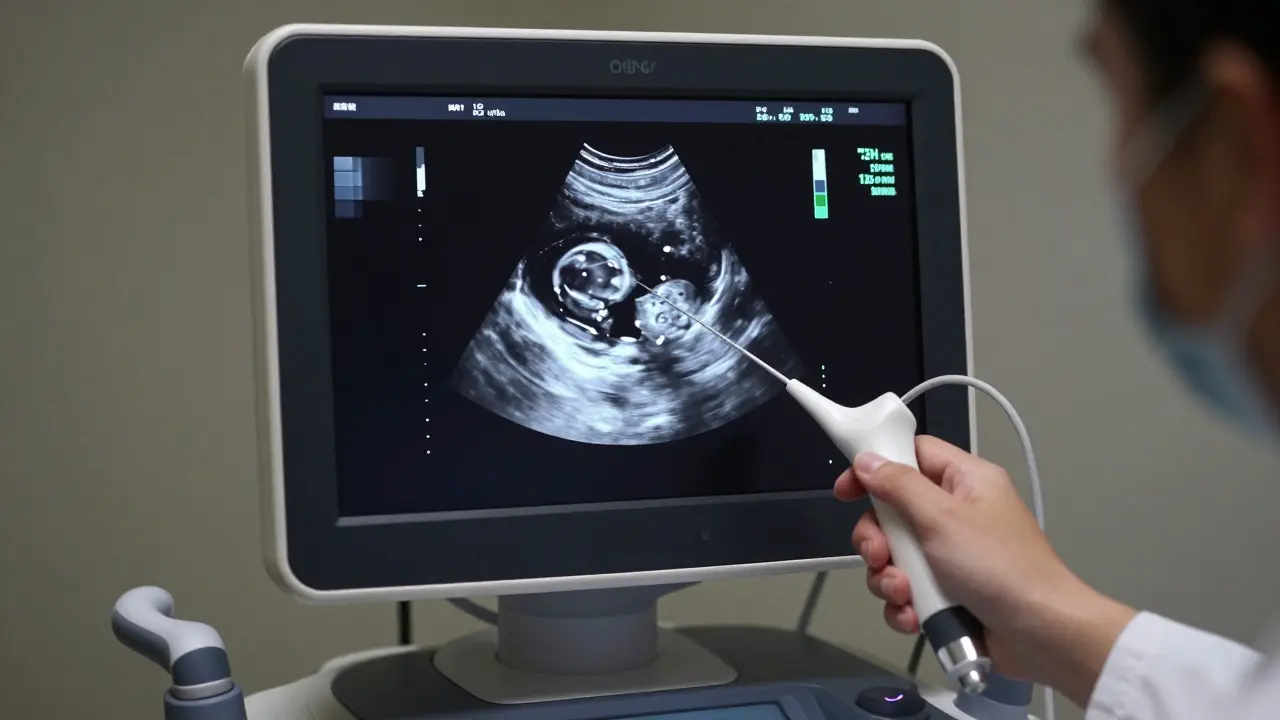

Monitor ultrazvového přístroje zobrazující detail vaječníku.

Mnohem přesnějším je transvaginalní přístup. Zde lékař zavede tenkou sondu přímo do pochvy, čímž se dostane k vaječníkům velmi blízko. Díky tomu vidí detaily, které by klasické rentgenové vyšetření přehlédlo. Co hledá? Především velikost vaječníků, přítomnost folikulů (vaječních pvůreků) a případné cysty. Zdravý vaječník má specifickou strukturu, která se mění během cyklu. V první polovině cyklu vidíme růst folikulů, ve druhé polovici pak žluté tělíčko, což je dočasná endokrinní žláza vznikající po ovulaci, která produkuje progesteron.